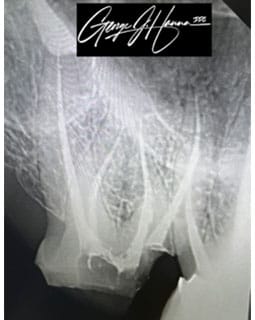

A frequent dental surgery called a root canal treats teeth that have a known infection or nerve damage. The technique involves extracting the pulp from the tooth to clear the infection.

The root canal process varies based on the patient but in most cases, the length of the nerve canal is left with a hollow hole as a result of this procedure. The hollow canal will subsequently be filled by the dentist.